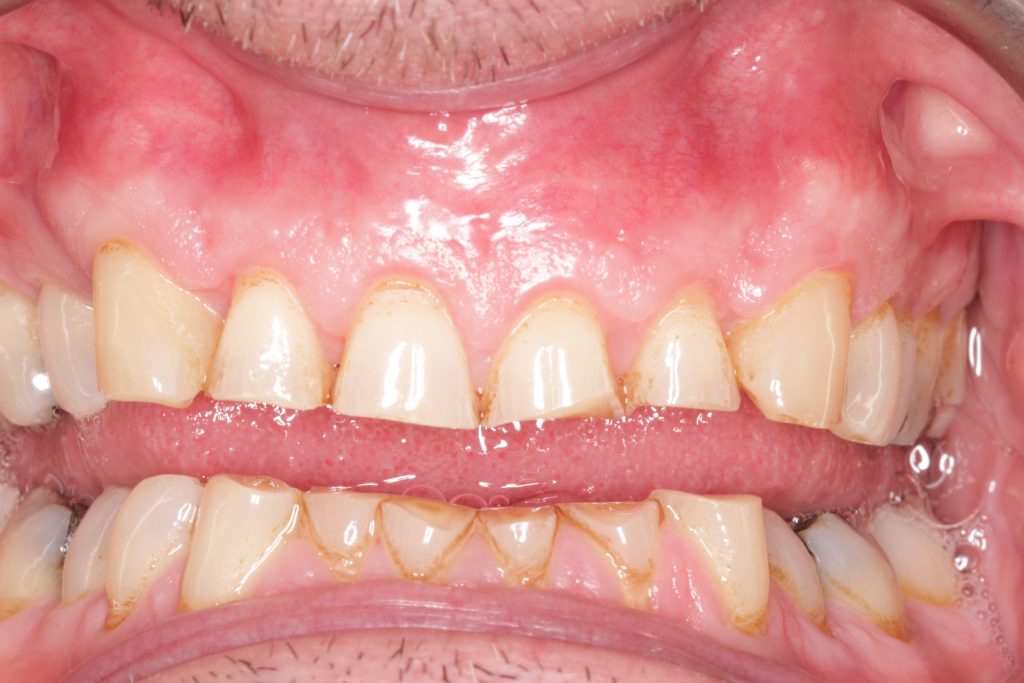

Initial presentation

A male 56-year-old presented with generalised tooth wear and has been a long-standing patient of the practice. He reported no pain or concerns until the extensive wear was highlighted in his examination.

He revealed that he has suffered nocturnal bruxism for many years and has noticed that his teeth have noticeably gotten shorter over the years believing that it was due to natural ‘wear and tear’.

- Alveolar compensation, maintaining occlusal vertical dimension (OVD)

- Shortened clinical crowns with pulp exposure imminent on lower anteriors

- Asymmetrical gingival zeniths

- Buccally positioned canines.